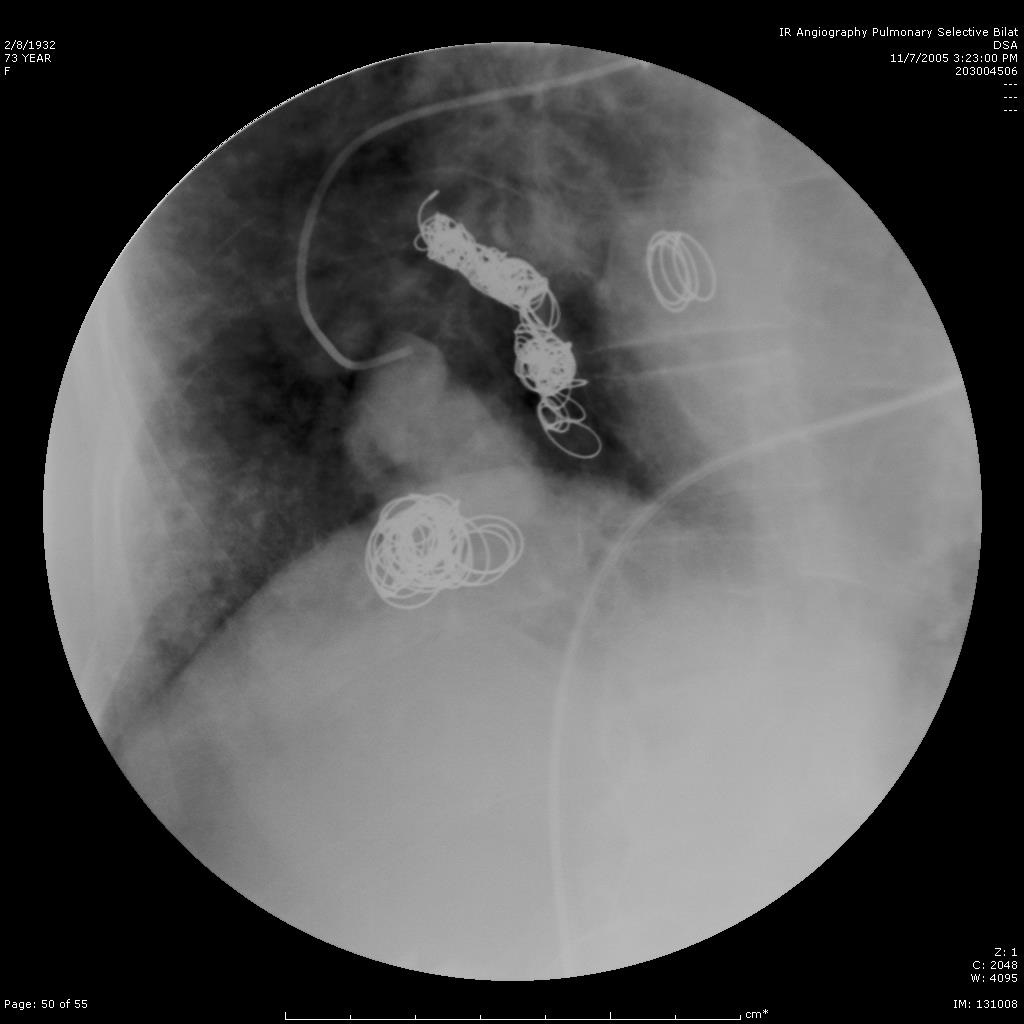

选择性肺动脉造影显示另一支滋养动脉和静脉池。 |

|

|

|

|

选择性进入滋养动脉 |

栓塞后弹簧栓子逸出至右肺静脉 |

栓塞后弹簧栓子逸出至右肺静脉 |

|

|

|

|

|

弹簧栓子在左心房“狂”跳 |

没啦? |

|

|

|

|

去哪儿啦? |

在这儿! |

造影 |

|

|

|

|

嵌在股深浅动脉分叉处 |

弹簧栓子被移除 |

继续栓塞 |

|

|

|

|

研究静脉池出口情况 |

寻找最佳工作位 |

静脉池出口直径大 |

|

|

|

|

静脉池出口直径大 |

放弃静脉池栓塞,仅栓塞滋养动脉 |

完成任务 |